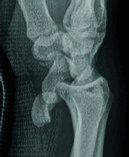

Palmar Divergent Dislocation of the Scaphoid and Lunate

Teaching Point: Palmar dislocation of the scaphoid and lunate is an extremely uncommon injury that warrants early diagnosis and treatment to avoid complications such as median nerve dysfunction, avascular necrosis, and premature osteoarthritis.